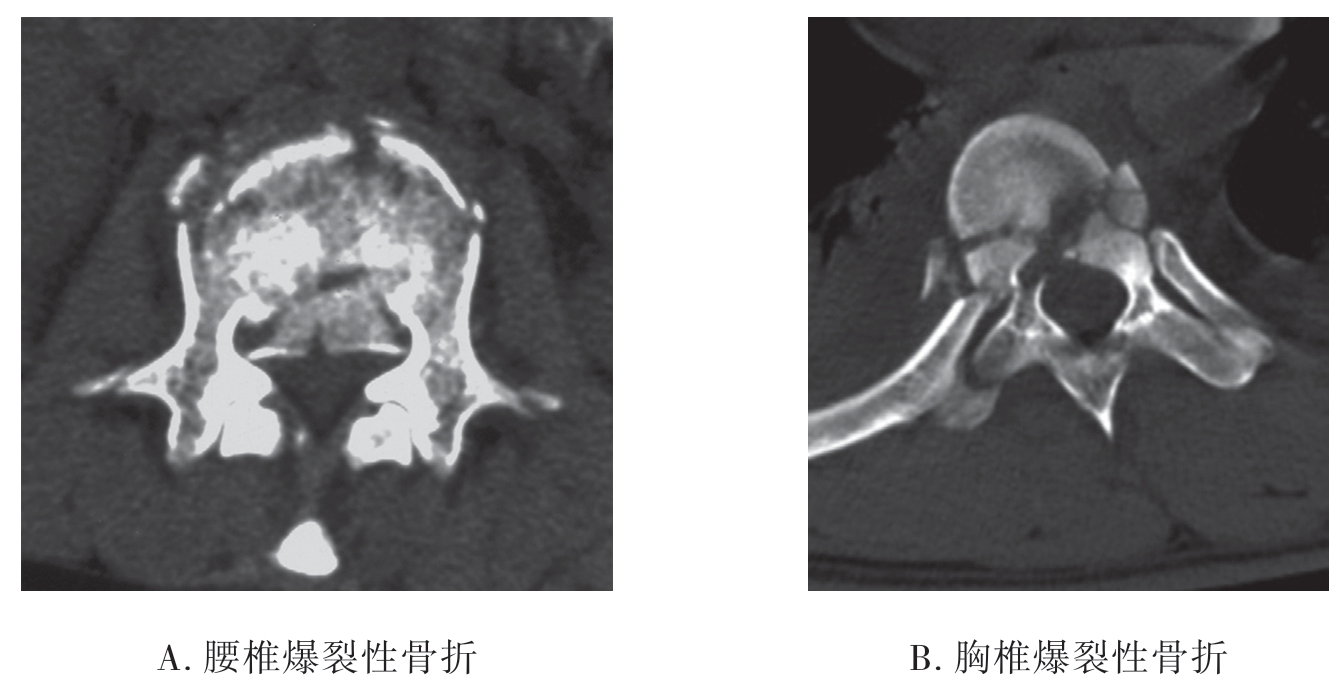

2.CT检查 脊椎骨结构复杂,互相重叠,CT应用图像后处理技术,可清晰地显示脊椎骨折类型、骨折片移位程度、附件骨折、小关节脱位、椎管变形及狭窄等变化。而CT检查的重点是观察脊髓有无受压情况。

(1)脊椎骨折:显示椎体、椎板、上下关节骨折及其移位,严重者椎管内可见骨碎片,椎管狭窄。

(2)椎管内血肿:①硬膜外血肿,血肿呈半圆形高密度影,硬膜囊变形较局限;②硬膜下血肿,血肿呈半圆形高密度影,形态不规则,边界不清楚;③脊髓内血肿,脊髓内高密度影,形态不规则,边界不清楚。

(3)创伤性椎间盘脱出:显示椎间盘局限性突入椎管使硬膜囊变形、脊髓移位(图7-2-15)。

图7-2-15 CT示爆裂性骨折